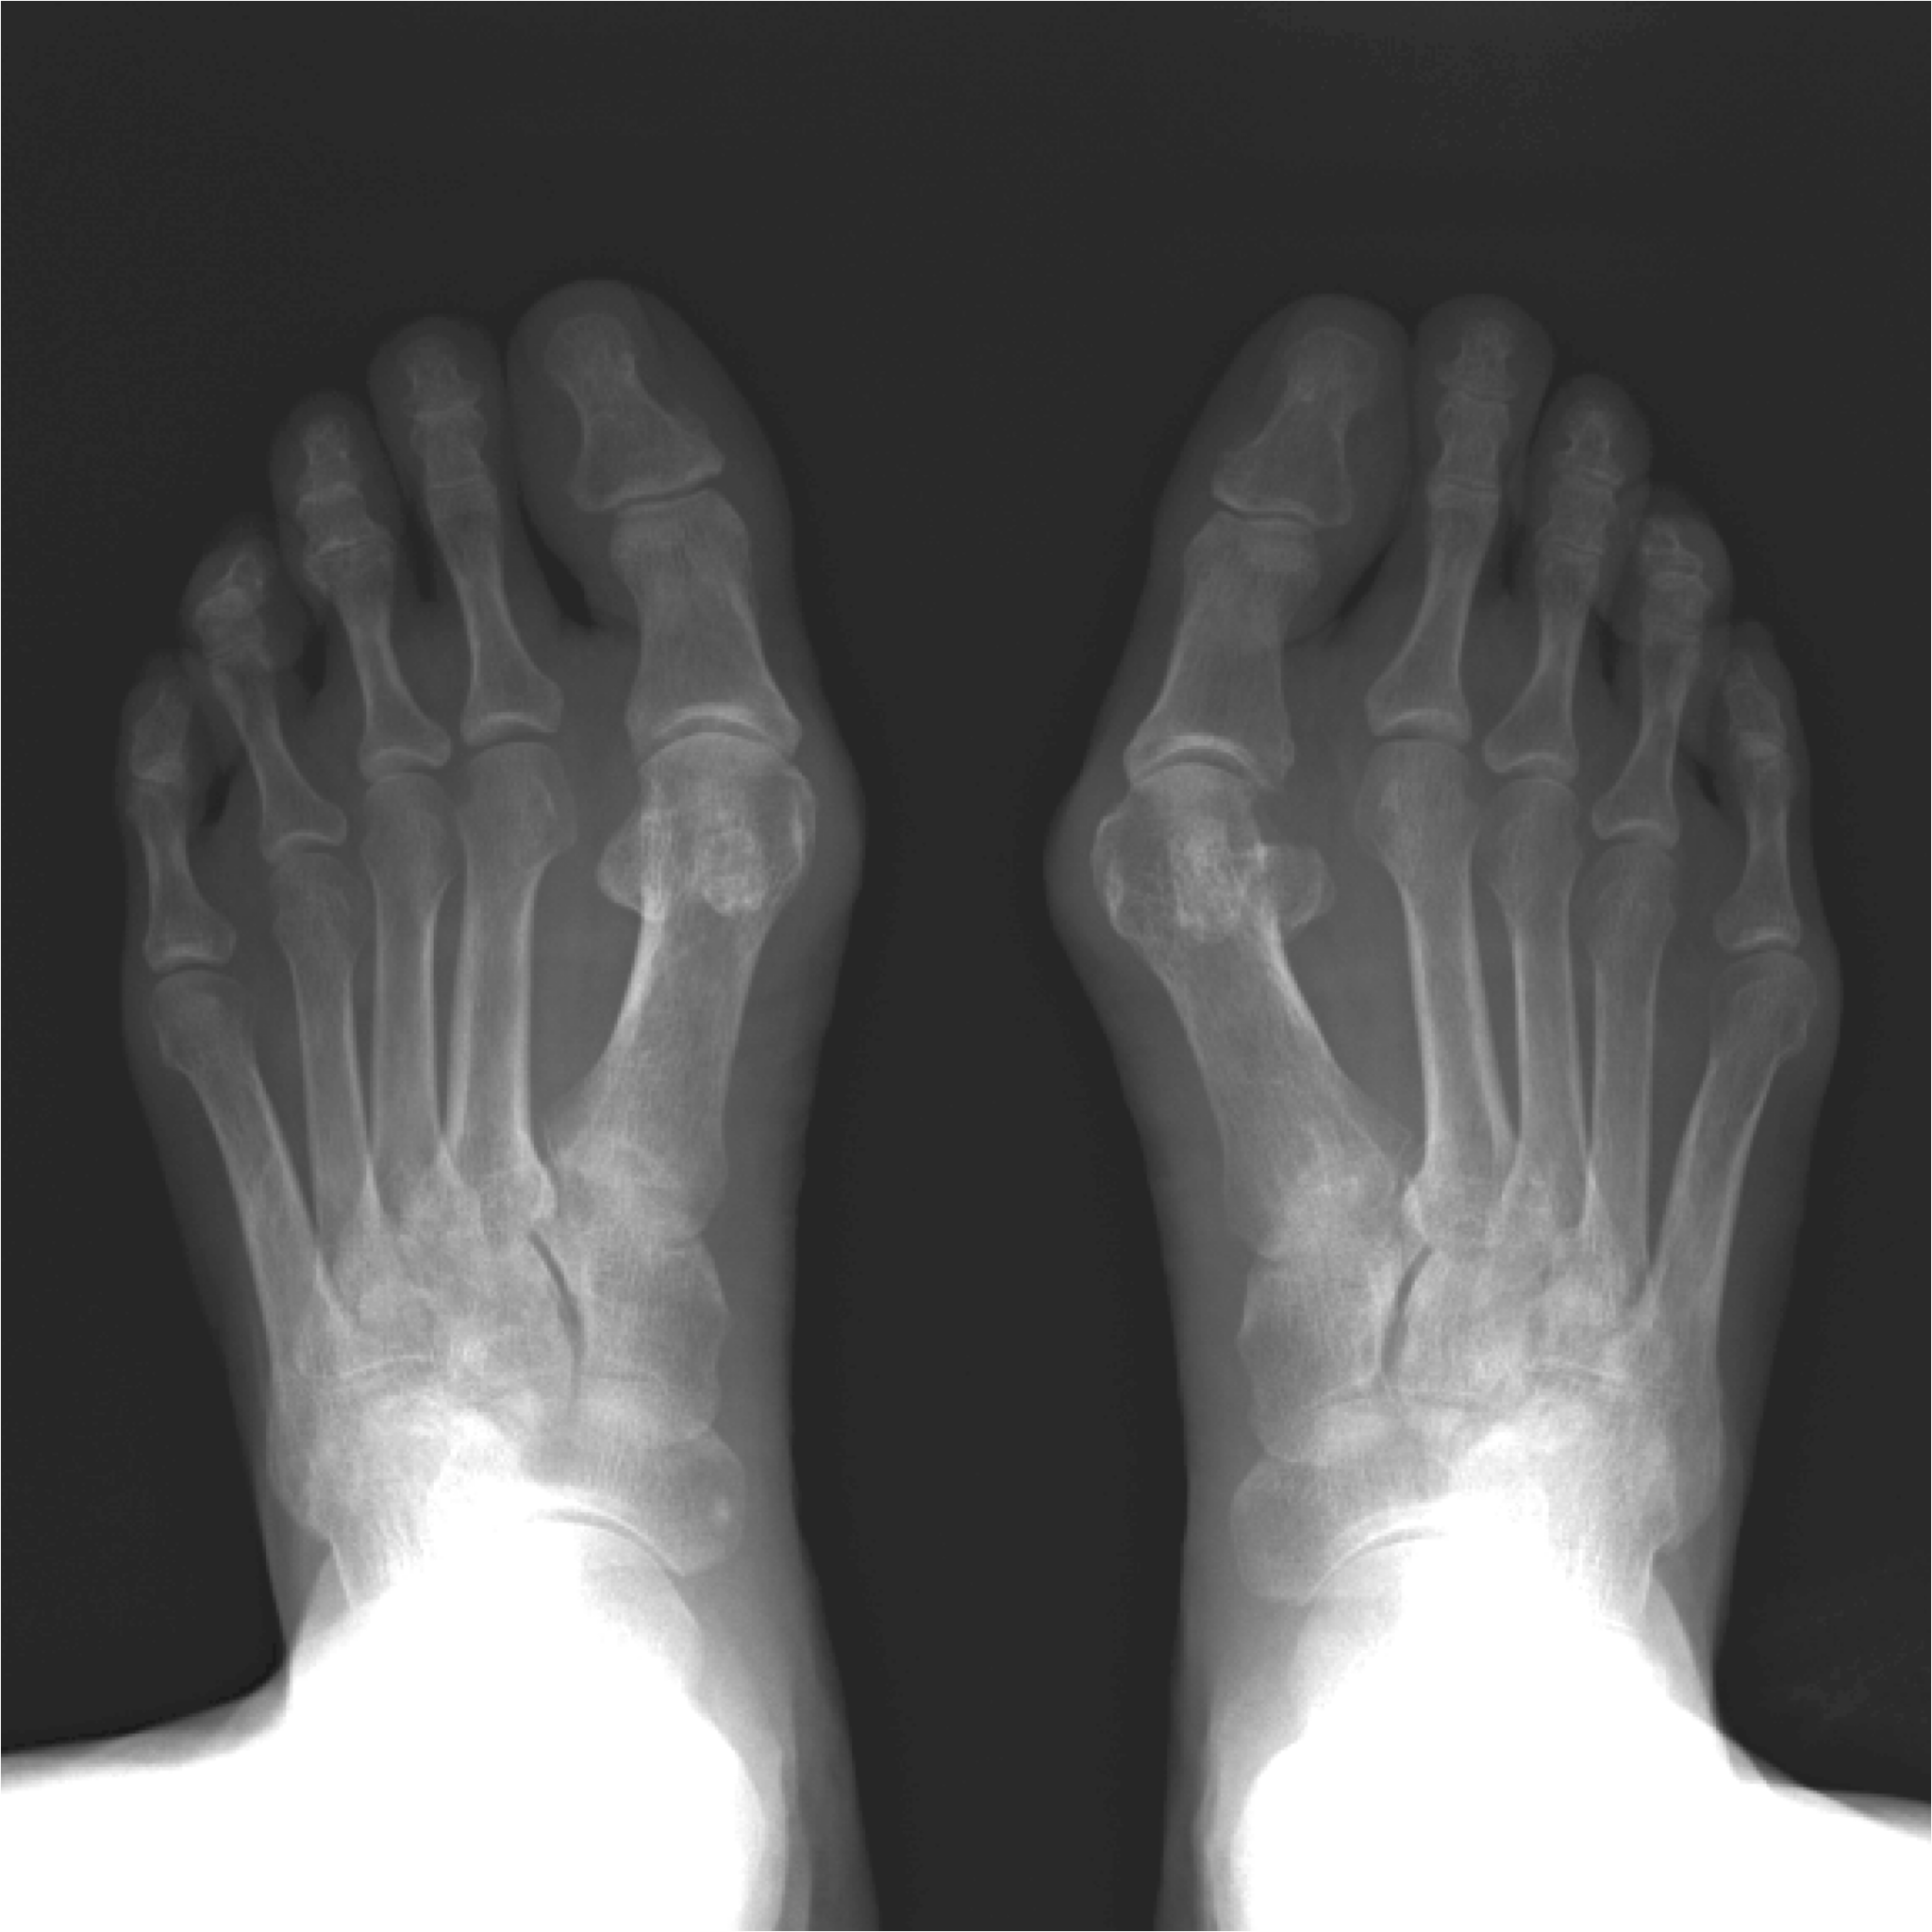

外反母趾の角度が大きいほど、前後方向の姿勢揺れが増える傾向

40歳以上の169名を対象にした調査では、

- 外反母趾の角度が大きい → 前後方向の姿勢揺れが大きい傾向

- 下肢筋量が少ない人ほど揺れが大きい

という結果が報告されています。

外反母趾のような“足指の変形”も、

姿勢制御に影響する可能性があることを示唆しています。